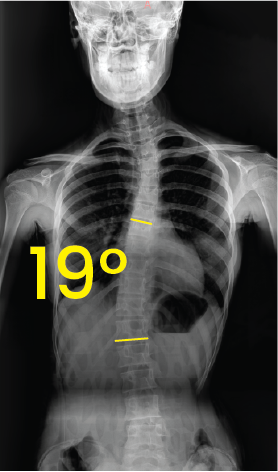

Toraks bölgesinde 43 derece açıyla eğri omurga gösteren röntgen görüntüsü.Göğüs ve omurga röntgeni, omurgada 19 derece eğrilik işaretiyle skolyoz gösteriyor.

Bel omurgasında 33 derecelik eğrilik gösteren skolyozlu insan göğüs ve karın röntgeni.Göğüs bölgesinde 17 derece eğiklik gösteren omurga röntgeni görüntüsü.